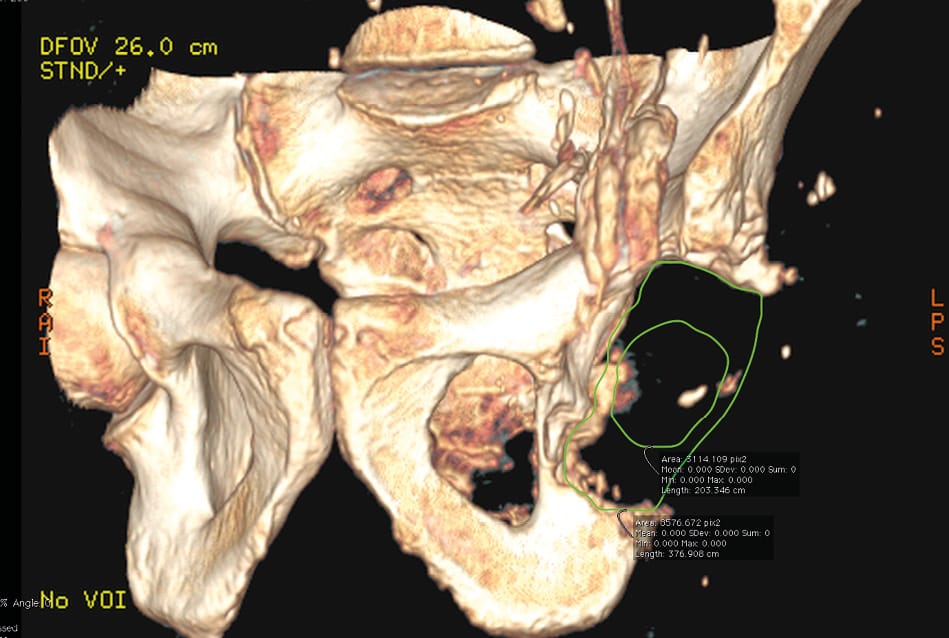

Initially, an acetabular roof plate or two plates was the method we used most. Now, they are no longer used. In every case that the planning allows it, we prefer to use screws in the acetabular roof, ischium and/or superior pubic ramus. More recently, we have chosen a single large calibre screw in the iliac isthmus. A potential alternative that could be considered is a central peg in the isthmus, but this was not used. This is because it is technically challenging to position the implant in the exact position planned and a 15-20° directional articulation plus oblong holes are integrated into the design for greater flexibility in aiming and fixation (Figures 3, 4 & 5). The only instrumentation required is an implant holder. There does not appear to be a need to use aiming devices or trial components.

Although the various classifications published, as we have seen, can be cross-referenced to determine the geometry of defects and define custom implant designs, they are not always particularly informative when planning how to anchor the implant (Figure 6, 7 & 8). In this respect, perioperative adaptation is often needed.